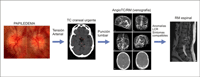

- Neuritis óptica anterior / papilitis

Se presenta con pérdida visual, defecto pupilar aferente y dolor periorbitario que aumenta con los movimientos oculares asociado a edema de papila. El estudio se dirige a las enfermedades desmielinizantes, principal etiología de las neuritis. La prueba de imagen de elección es la RM craneal y orbitaria con finalidad diagnóstica, pronóstica (mayor riesgo de desarrollar esclerosis múltiple si aparecen lesiones características), y evolutiva (el realce de las lesiones con contraste sugiere enfermedad en fase aguda). Las secuencias FLAIR son las más adecuadas para mostrar las lesiones desmielinizantes (Figura 4). La RM orbitaria puede obviarse en casos muy típicos de neuritis con lesiones desmielinizantes en la RM craneal.

Figura 4. Izquierda: edema de papila en neuritis óptica típica. Centro: lesiones desmielinizantes en RM craneal (T2). Derecha: engrosamiento del nervio óptico izquierdo en RM orbitaria (T1)

En los casos atípicos sigue estando indicada una RM craneal y orbitaria, asociando otras pruebas complementarias según la sospecha diagnóstica (serologías, marcadores de autoinmunidad, punción lumbar, etc.). Las secuencias T1 con supresión grasa son las más adecuadas para apreciar el realce en la porción orbitaria del nervio óptico. La RM espinal se indica por la sospecha de neuromielitis óptica: episodios recurrentes de neuritis óptica anterior o retrobulbar con menor recuperación visual de lo esperado, asociados o no a mielitis transversa, y cuya RM craneal no es compatible con esclerosis múltiple (EM) (Figura 5).

Figura 5. Neuromielitis óptica